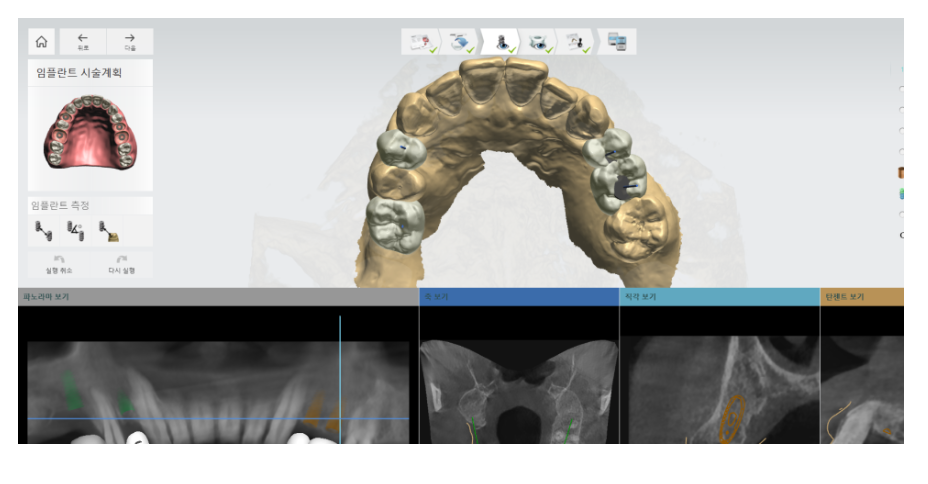

하지만 요즘은 수술 전부터 디지털 장비로 수술 경로를 설계하고,

그 설계대로 정확하게 식립하는

네비게이션 임플란트가 주목받고 있습니다.

CT와 구강스캐너 데이터를 바탕으로

정확한 각도, 깊이, 위치를 미리 계획하고,

그 계획대로 식립할 수 있도록 디지털 수술 가이드를 제작해 진행합니다.

수술 시 제작된 가이드를 입안에 착용하고 진행하죠.

가이드에는 사진 처럼 구멍이 뚫려있습니다.

임플란트 수술이 계획된 위치인데요.

그 공간에 임플란트를 정확히 식립합니다.